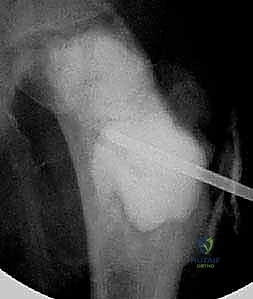

تُظهر هذه الأشعة السينية (X-ray) كيس عظم أحادي الغرفة (UBC) في الجزء العلوي من عظم العضد. لاحظ كيف أن الكيس يسبب ترققاً في قشرة العظم دون أن يخترقها.

- في الـ UBC، تظهر الآفة كمنطقة شفافة (سوداء) مركزية داخل العظم. وهناك علامة مميزة تُسمى "علامة الورقة المتساقطة" (Fallen Leaf Sign)، حيث تسقط قطعة صغيرة من قشرة العظم المكسورة داخل الكيس المملوء بالسائل، وهي علامة مؤكدة بنسبة 100% تقريباً على الـ UBC.

في الـ ABC، تظهر الآفة غير مركزية، متمددة، وتدفع قشرة العظم للخارج لتصبح رقيقة جداً مثل "قشرة البيضة".